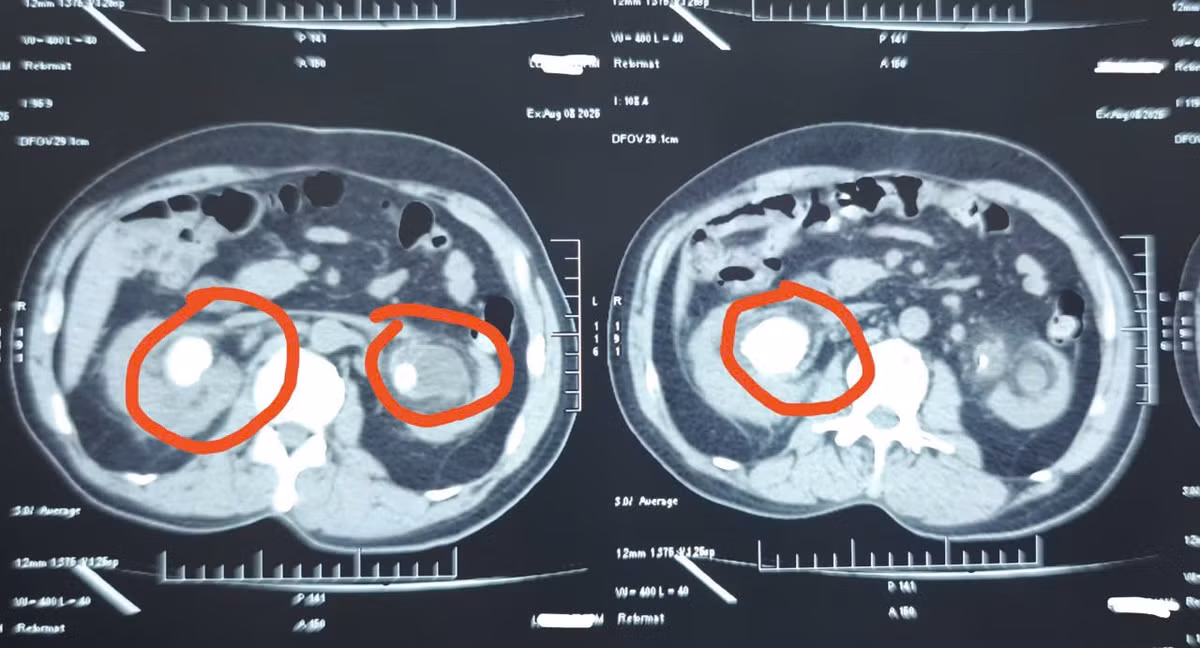

“Qua thăm khám, chúng tôi không thể rút sonde JJ bằng biện pháp thông thường. Do thời gian lưu sonde quá lâu, bệnh nhân được chỉ định chụp CT. Kết quả cho thấy sỏi bám vòng quanh sonde JJ chiếm gần như hết diện tích đài bể thận 2 bên. Thận phải có viên sỏi lớn 34x29mm, thận trái 20x13mm kèm nhiều viên nhỏ rải rác. Sỏi ở trên thận gây ứ nước thận độ 3.

Hình ảnh sỏi thận trên phim chụp - Ảnh BVCC